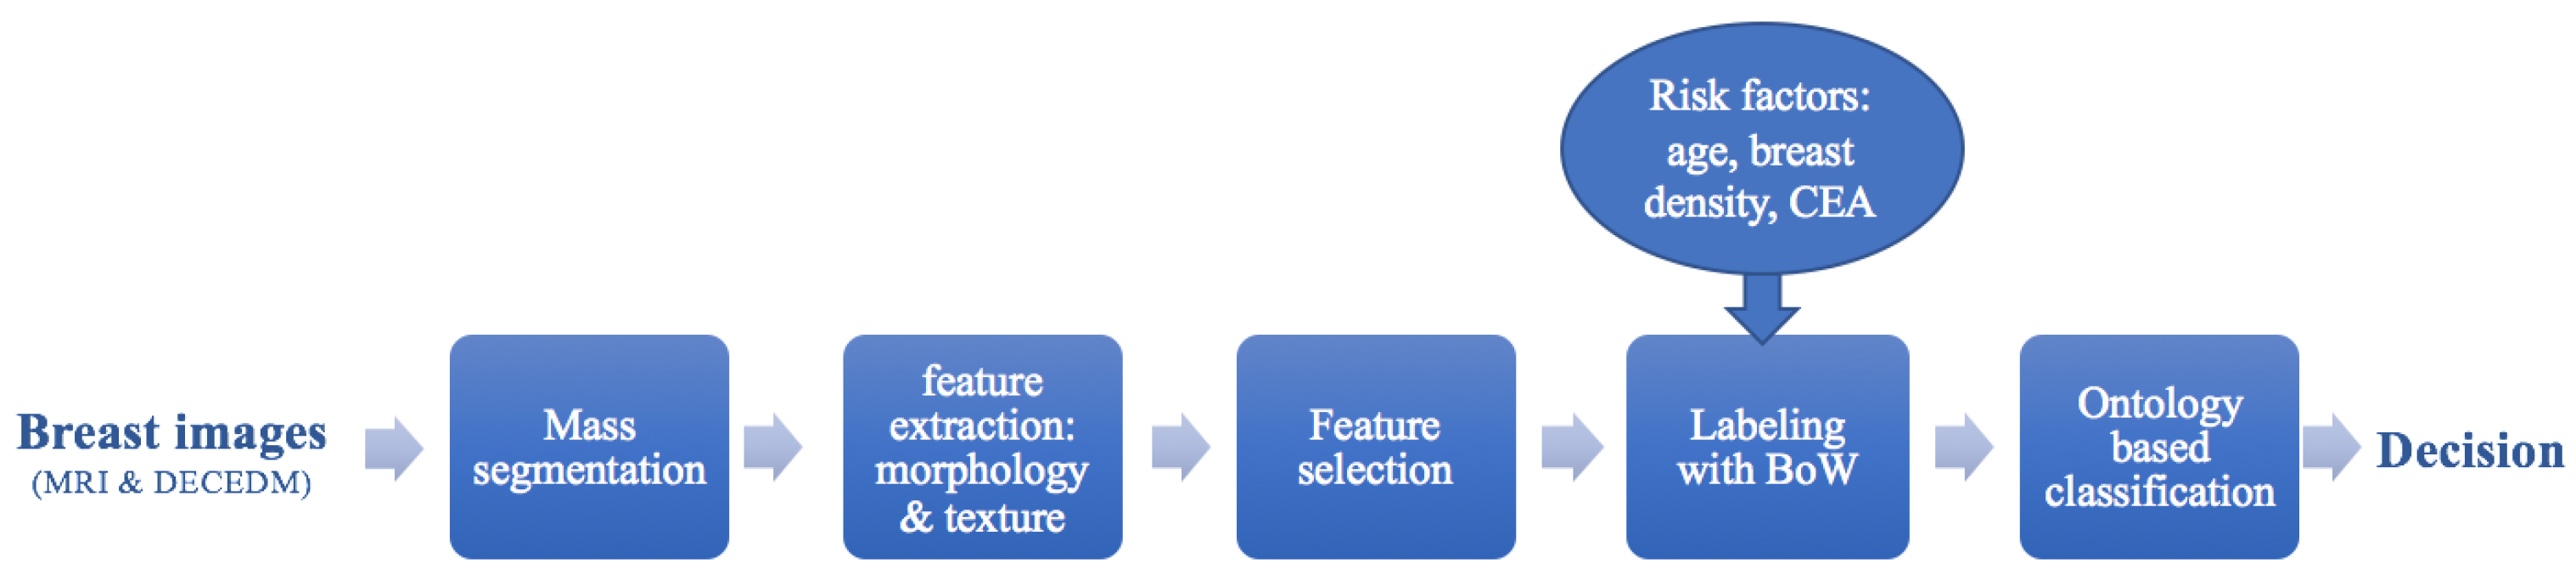

2.3. Feature Selection

3.3. A Comparison between Choquet Intagral for Feature Selection and Other Selection Method

3.3.1. Structural Selection

3.3.2. Inter-Modal Selection